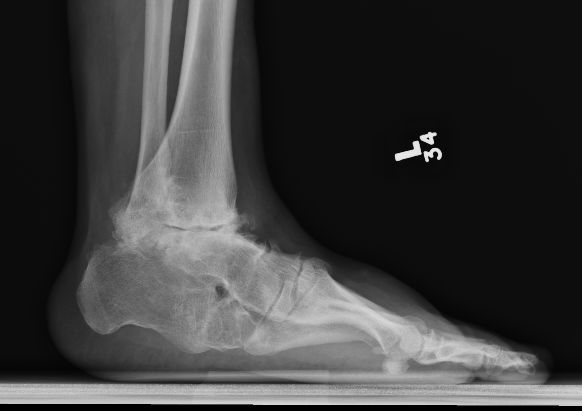

Combined ankle and subtalar joint osteoarthritis

Talar AVN

Severe Deformity - acquired flat foot / neurological conditions / Charcot /

Severe acquired planovalgus